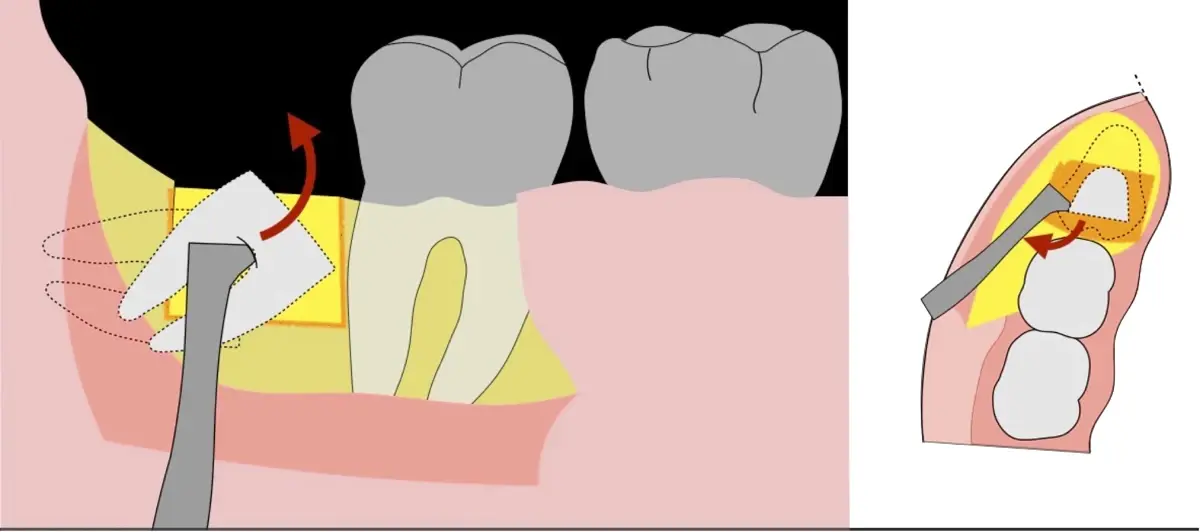

El procedimiento puede variar en su complejidad dependiendo de su ubicación, profundidad, angulación, y la densidad ósea circundante.2 Uno de los pasos más críticos y cruciales en la extracción es la osteotomía previa y concomitante al acceso quirúrgico del diente, para lo cual se utilizan diversos instrumentos como cinceles y martillos, instrumental rotatorio o de corte por ultrasonido.3

El instrumento piezoeléctrico utiliza un corte micrométrico que retira un área de superficie mínima de hueso, y reduce el riesgo de termonecrosis marginal en comparación con las fresas rotatorias convencionales.

En contraste, el instrumento piezoeléctrico utiliza un corte micrométrico que retira un área de superficie mínima de hueso, y reduce el riesgo de termonecrosis marginal en comparación con las fresas rotatorias convencionales.9 Los micromovimientos mejoran la precisión en el corte y el control táctil, y eliminan las macrovibraciones que se producen con los instrumentos rotatorios.10 Su frecuencia de oscilación es la amplitud de 60-200 μm horizontalmente y de 20-60 μm en sentido vertical, lo que es muy inferior en comparación con las micro sierras oscilantes; por lo tanto, proporciona cortes de osteotomía precisos y seguros. Adicionalmente, posee vibraciones ultrasónicas que descomponen el líquido de irrigación en partículas muy pequeñas (fenómeno de cavitación, que produce un efecto hemostático y así reduce la pérdida de sangre), lo que proporciona una visión clara y sin obstáculos del campo quirúrgico11,12.